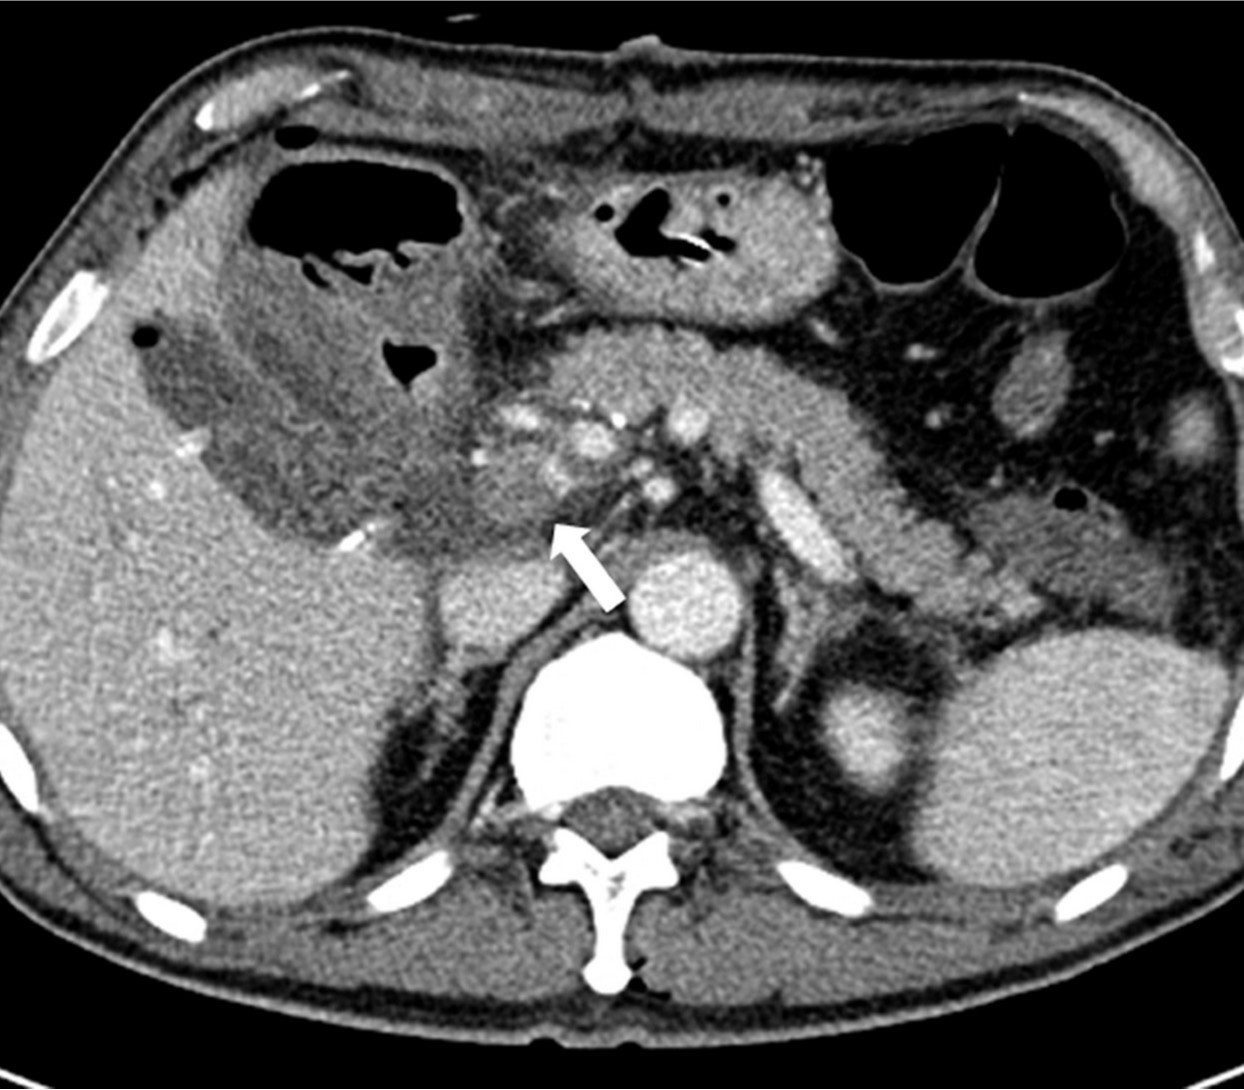

Figure 1. Contrast-enhanced CT scan following segmental resection of bile duct with Roux-en-Y hepaticojejunostomy and segmental resection of portal vein with end-to-end anastomosis. Both axial (A) and coronal (B) studies show a thrombus (arrows) in the narrowed main portal vein and peripheral portal flow is not seen.

총담관과 간문맥 분절 절제 및 루엥Y 간공장문합술 시행 3일 후 촬영한 간 도플러 초음파에서 문맥의 혈류가 관찰되지 않았으며 주문맥을 비롯하여 양측 문맥에 동일에코의 결절들이 있어 혈전증으로 생각되었음. CT에서도 주문맥이 혈전에 의해 폐쇄되어 있어 원위부 문맥 혈류가 보이지 않았음(Fig. 1).